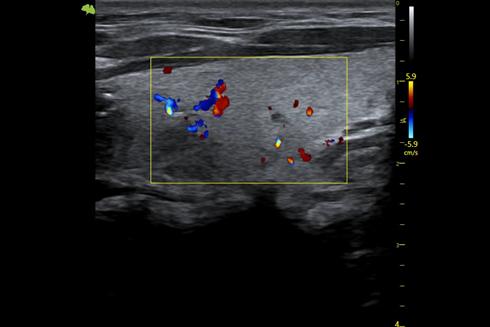

3. Công nghệ Doppler màu VFlow tiên tiến với độ nhạy cao hơn có thể giúp phát hiện ngay cả các mạch máu ngoại vi. Điều này cho phép chẩn đoán chính xác khi việc kiểm tra lưu lượng máu đặc biệt khó khăn.

Vinno S100 còn được trang bị công nghệ đầu dò đơn tinh thể PureWave kết hợp XCen, mang lại băng thông rộng hơn, độ nhạy cao hơn và khả năng xuyên sâu tốt hơn. Nhờ đó, hình ảnh thu được không chỉ rõ nét mà còn chi tiết ở cả những vùng sâu trong cơ thể. Công nghệ Doppler màu tiên tiến cũng giúp đánh giá chính xác lưu lượng máu, hỗ trợ hiệu quả trong các trường hợp lâm sàng phức tạp.